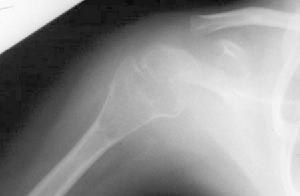

骨質疏鬆骨質疏鬆資料

骨質疏鬆2、骨質疏鬆症的藥物治療